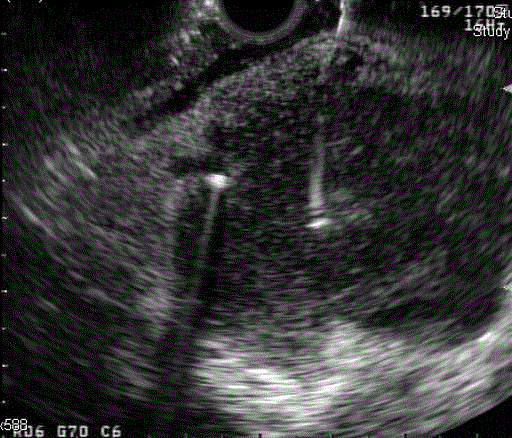

Figure 3. Endoscopic ultrasound showed a large hypoechoic somewhat lobulated appearing mass approximately 3.8 cm in size involving most of the head of the pancreas.